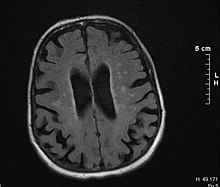

BrainAtrophy(exvacuo).png

Brain atrophy on MRI from vascular dementia